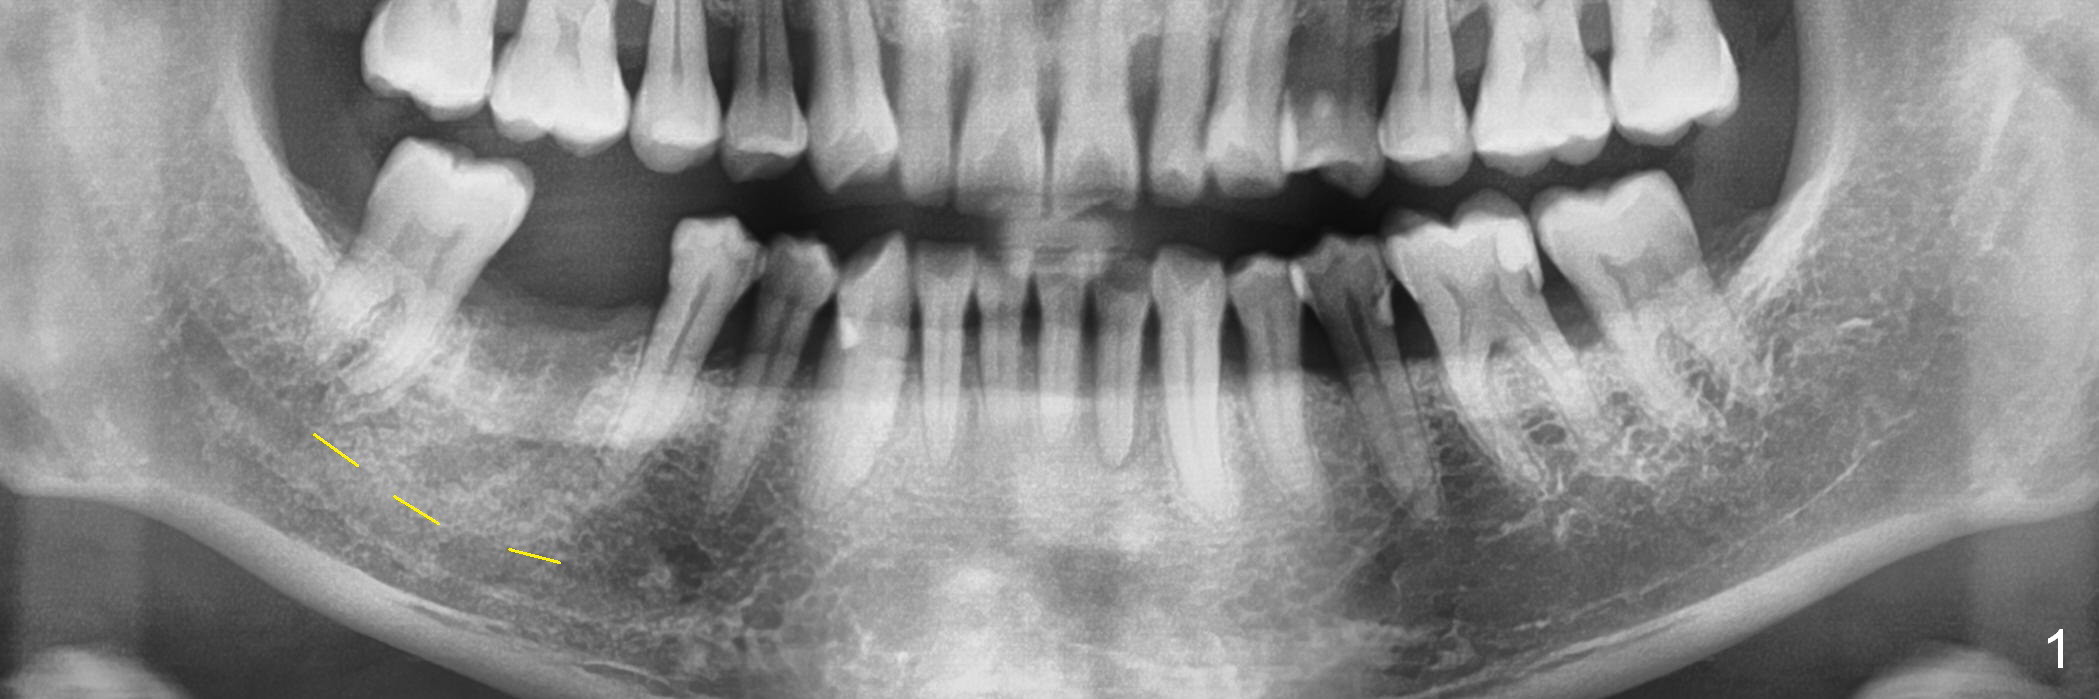

A 44-year-old man lost the tooth #30 three months ago. He is very nervous about the Inferior Alveolar Nerve (Fig.1,3 yellow dashed line). Offer Valium if needed. Check whether there is DO caries of the tooth #29 (Fig.2 <). Finish composite if indicated. There is mild to moderate buccal plate atrophy. The implant may have to be placed slightly lingually. When the insertion torque is high, place an abutment (Fig.3 white inverted cup) with subgingival margin (arrowheads: gingival margin) so that the emergency profile of the crown is better. Make an ideal immediate provisional with good emergency profile and place sutures. The mesial bone may have to be trimmed (Fig.4 red area) so that the abutment is able to be seated without interference. Take photo at each step.